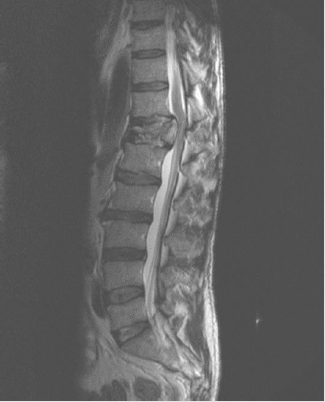

Figure 6: T12 fracture by accident with car overturning, posterior migration of the vertebral body, with spinal section.

It is a drama film directed by Oliver Nakech and Eric Toledano. Story inspired by the life of a rich Count Phillippe Pozzo di Borgo Author of the book “Le Second Soulffle”. Two characters, totally opposites are a rich, educated and very intolerant Francoiz Cluzet parapejico since 1993 due to a paragliding accident and his relationship with Omar Sy immigrant from Senegal, with criminal record. The high traumatic medullary section (MS)) can lead to a spectrum of neurological problems, including loss of motor and sensory function, bowel and bladder dysfunction, spasticity, neuropathic pain and autonomic dysreflexia. Signs of suspected spinal injury include limb weakness or paralysis, alterations in trunk or limb sensitivity. Hypophonia (difficulty in language issuance), abdominal breathing, hypotension and paradoxical bradycardia, position in flexion of the paresthesia elbows, pain, deformity in the spine and priapism (Figures 2&3).